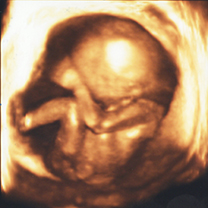

3Dエコー/4Dエコー(4D超音波)

- エコーの写真は、差し上げておりますが、動画が欲しい方は、エコー機のモニター画面のみに限り、患者様が持参されたスマホやビデオで撮影していただく事が可能です。(院内の別の場所やスタッフ、他の患者様などは、撮影しないでください)

- 当院で妊婦健診を行っている方は、13週以降、毎回3D/4Dエコーを行います。(追加料金はありません)

- 他院で妊婦健診を行っている方は、1回10分程度の検査で、料金は4300円です。

- 3D/4Dエコーに適している時期は妊娠15週~29週頃です。

- エコーは、ご主人やお子様、ご両親など家族の方と一緒にご覧になることが可能です。

*条件により赤ちゃんの顔が、見えない場合もあります。